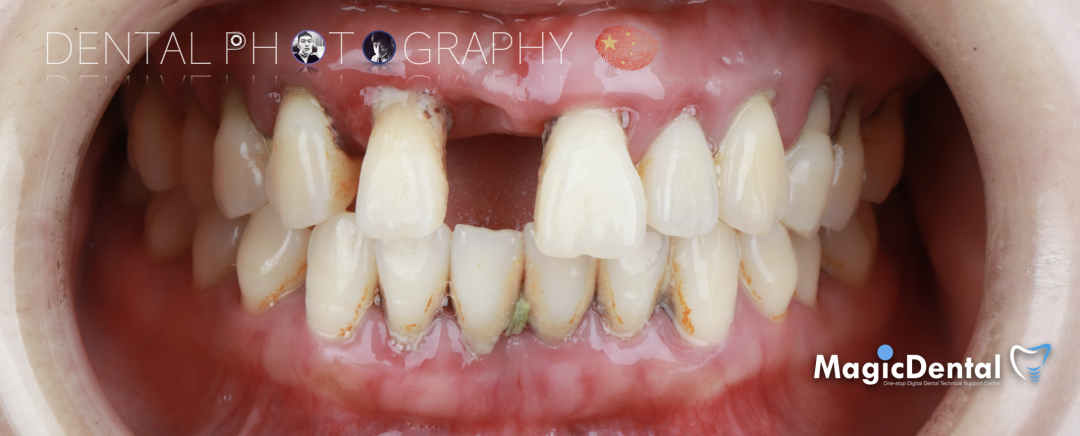

患者术前口内及面相照片

患者:32岁女性患者。

主诉:牙齿松动要求治疗。

现病史:患者两年前发现牙齿逐渐松动,近一个月左上前牙脱落,且上颌牙齿无法咀嚼,现来我院就诊要求治疗。

既往史:既往体健,无其他系统病史,否认重大疾病史,有口腔拔牙史。

口腔检查:口腔卫生差,全口牙龈红肿,牙颈部大量牙结石附着,伴有不同程度附着丧失,牙周探针深度普遍大于8mm,上颌牙列I~III°松动。

诊断: 全口慢性牙周炎,上颌牙列缺损。